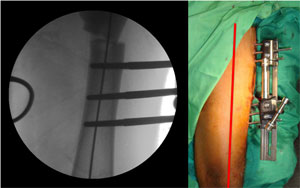

The C-arm picture on the left and the clinical picture showing the perfectly aligned axis. |